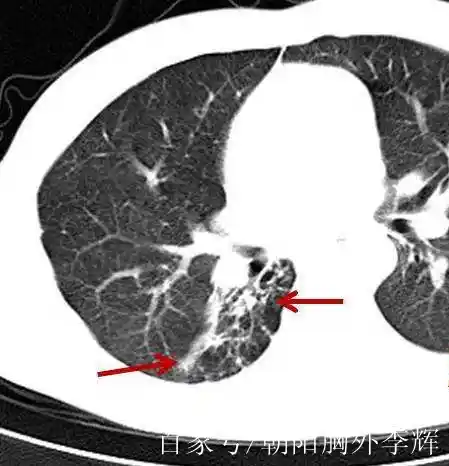

纤维条索影是医学影像学上的一个术语,通常在胸部X光或CT扫描中出现,表现为一条或多条细线样的影像。这种影像的病理基础是纤维组织的存在,它们可能来源于纤维母细胞、血管内皮细胞、结缔组织等的增生。纤维条索影的形成通常与以下几种情况有关:

- 慢性感染:如肺结核或肺炎后,经过治疗,病灶吸收后可能遗留下瘢痕,形成纤维条索影。

- 炎症:长期慢性刺激下,肺部组织可能形成陈旧性病灶,常见于肺结核患者或肺炎、支气管炎患者。

- 既往病变:纤维条索影可能是既往病变经过治疗或自身防御反应后,大部分吸收好转,仅遗留有纤维化部分的表现。

- 其他原因:包括支气管扩张、慢性阻塞性肺疾病、肺纤维化以及长期吸烟的人群也可能表现出纤维条索影。

纤维条索影本身通常不会对肺功能造成严重影响,范围较局限,对肺组织损害较小,患者的肺功能检测也基本正常。然而,如果纤维条索影较多,且患者有长期吸烟史或其他症状,如咳嗽、咳痰、呼吸困难等,可能需要进一步的评估和治疗。重要的是,纤维条索影不应与肺部间质性改变混淆,因为它们在发病机理上有很大的区别。如果患者发现有纤维条索影,建议保持正常心态和良好的生活习惯,戒烟,避免空气污染,并注意个人防护。